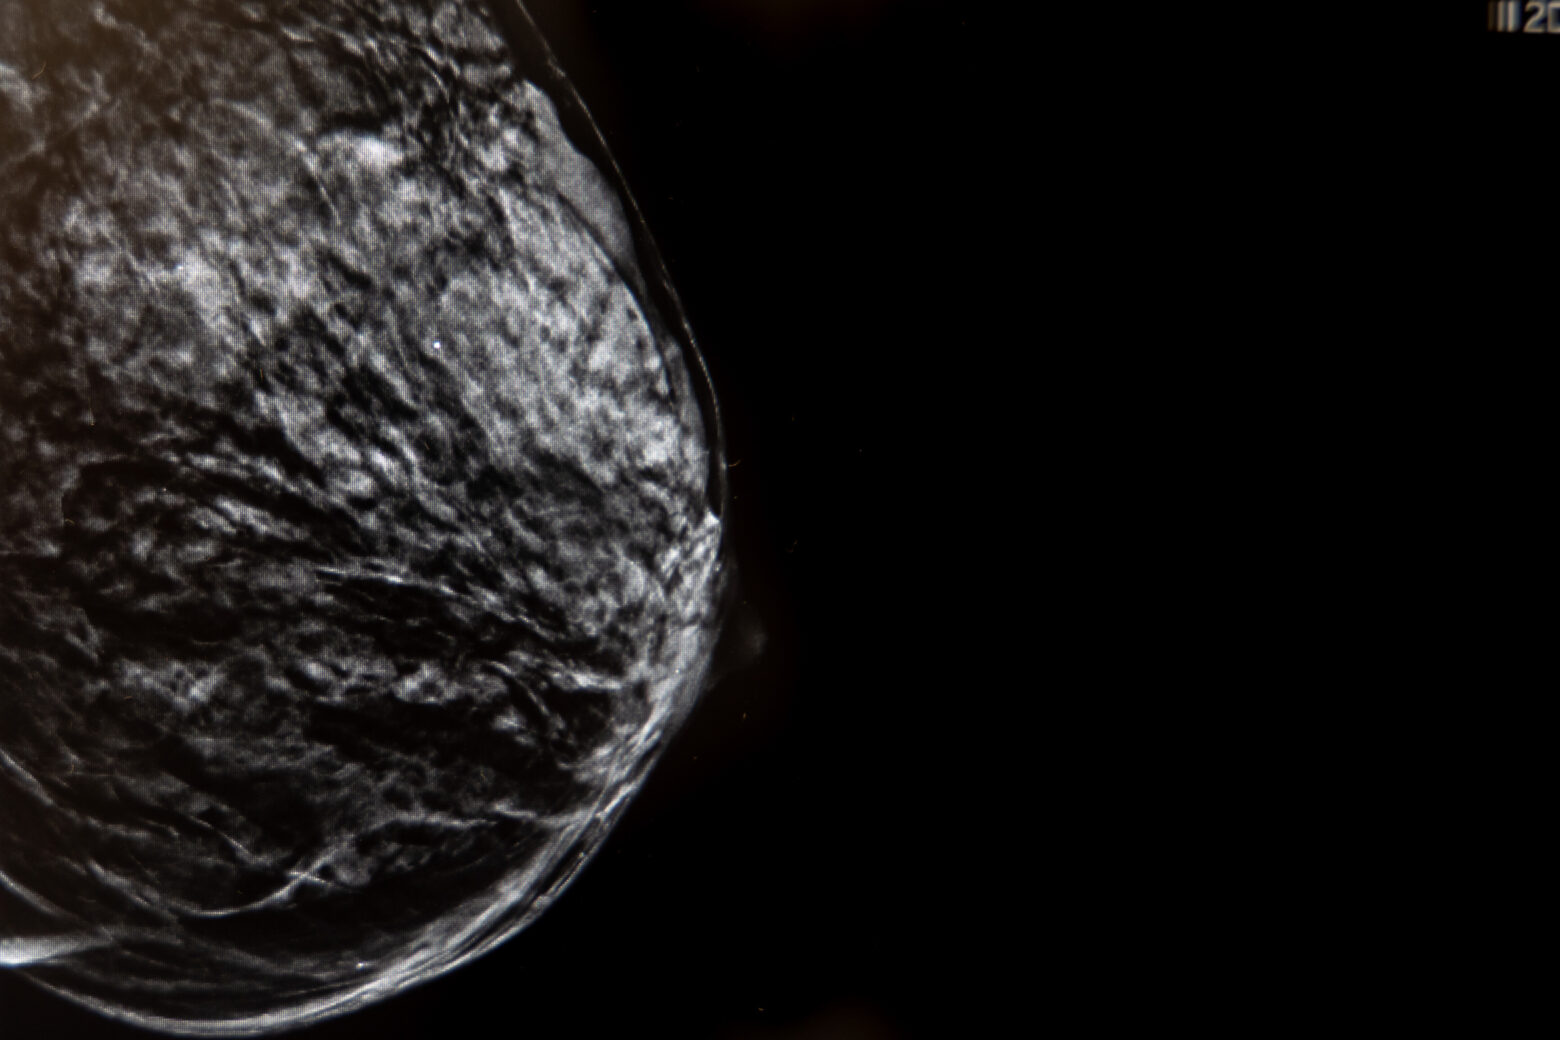

Uno de los mayores avances en el diagnóstico mamario es la imagen 3D (Tomosíntesis) que consiste en la adquisición de imágenes de baja dosis de radiación.

La colocación de un arpón de mama se realiza con guía ecográfica o mamográfica. El radiólogo utiliza el ecógrafo o el mamógrafo para visualizar la lesión en tiempo real y dirigir el arpón con precisión.